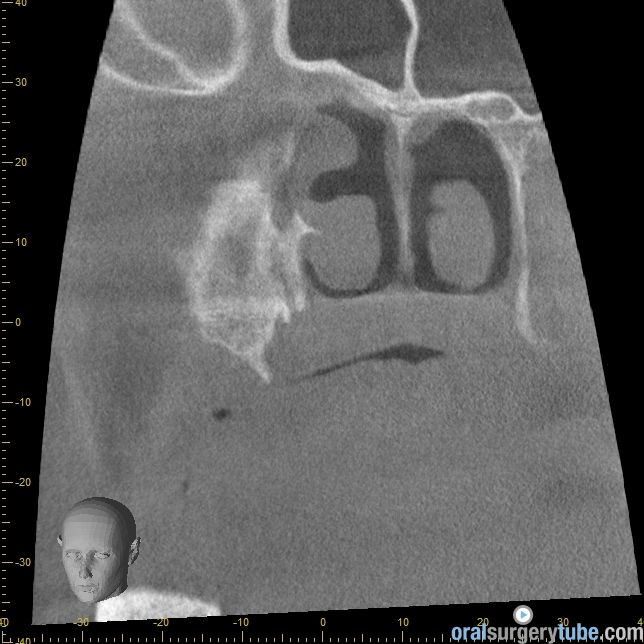

Cierre de comunicación orosinusal con tejido duro y blando